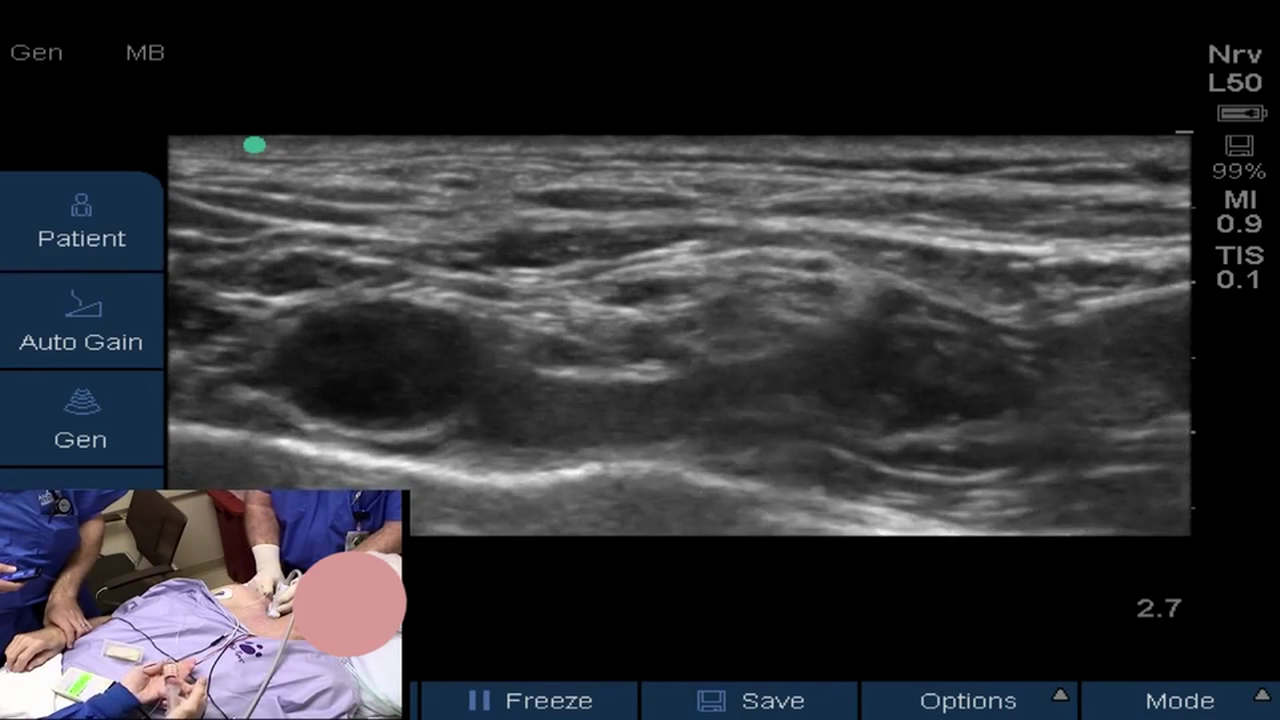

• How to Perform an Ultrasound-Guided Supraclavicular Nerve Block

Dr. Stuart Grant, Professor of Anesthesiology at Duke University, describes the anatomy, equipment and technique for the successful placement of an ultrasound-guided supraclavicular nerve block.